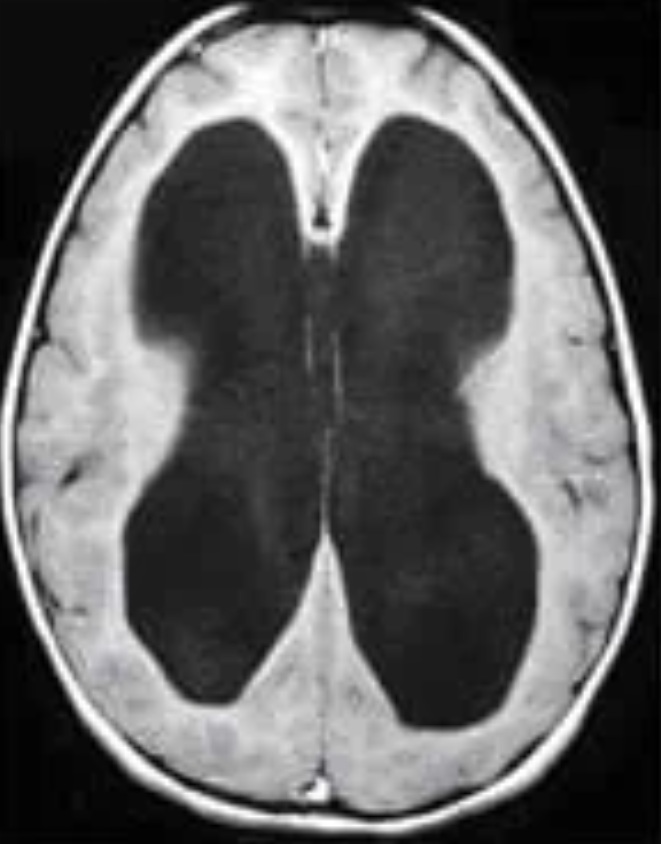

Imagen ilustrativa de hidrocefalia

Hidrocefalia

Estudio etiológico, manejo valvular y seguimiento clínico-radiológico a largo plazo.